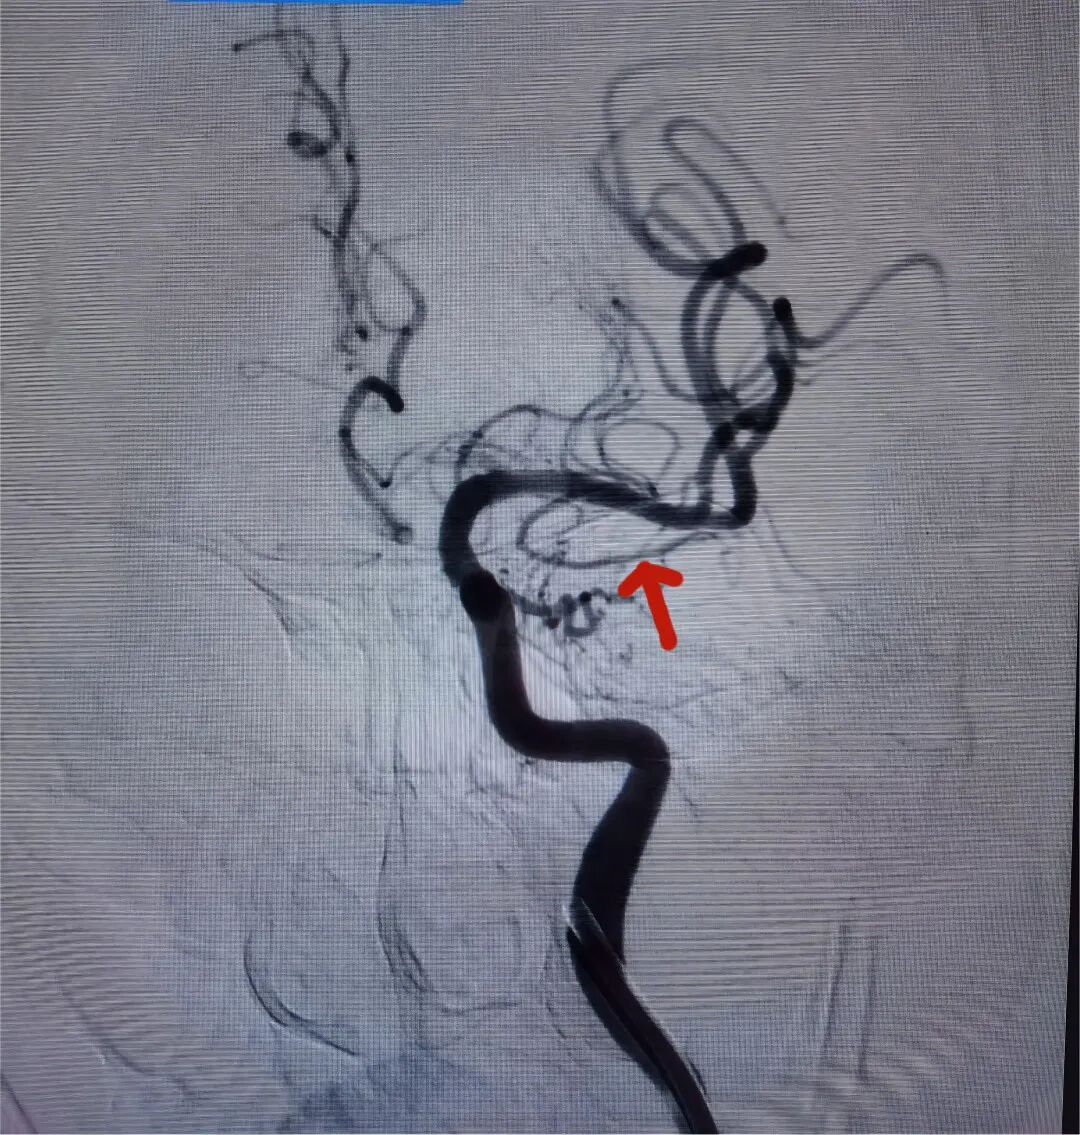

陈阿姨术前颈动脉CTA及DSA

陈阿姨术后DSA